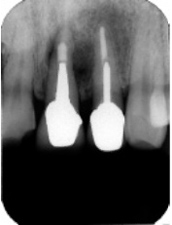

インプラント埋入後X線写真